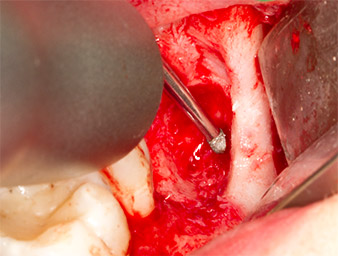

Utilizzando uno strumento per lo sbrigliamento periodontale (Piezomed P1), lo spazio del legamento periodontale della radix relicta è stato quindi ampliato minimamente (Fig. 8).

Lo stesso strumento attivato è stato inserito nel canale della radice per allentare il frammento con le vibrazioni micro-oscillatorie (Fig. 9-10).

Piezomed P1

Fig. 9: Lo strumento Piezomed P1 è consigliato dal produttore principalmente per lo sbrigliamento periodontale ma è anche adatto a scopi chirurgici. Qui lo vediamo posizionato sul canale della radice dopo un minimo ampliamento dello spazio del legamento periodontale.

Fig. 10: Grazie alla sua forma sottile, lo strumento può penetrare nel canale della radice e rimuovere il residuo di radice tramite la micro-oscillazione (vibrazione).

È stato quindi possibile rimuovere il residuo di radice di lunghezza approssimativa di 6 mm in un unico pezzo, con l'accessorio P1 (Fig. 11).